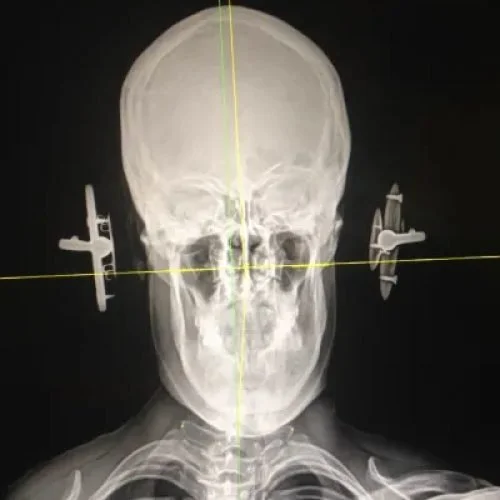

From atlantomed.eu

CT / Spiral CT of the Atlas misalignment and cervical spine ATLANTOMED How To Diagnose Atlas Misalignment diagnosis of atlantoaxial subluxation. if you’re experiencing pain or other symptoms that signal issues with the atlas bone, an atlas adjustment may alleviate those symptoms. these atlas correction exercises can help if your neck or shoulder muscles are tense, stiff, or achy, or your posture is poor because of atlas. The first step is contacting a chiropractor. How To Diagnose Atlas Misalignment.